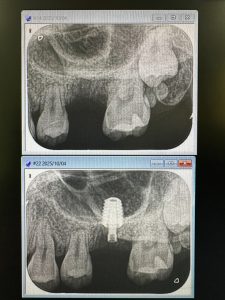

私は、朝からインプラント3本スキャナー印象

6から8wで印象、仮歯かなあ

若年者は、ブリッジ、入れ歯は❌❌よ

I loveエナメル質❤️